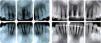

DIAGNOSISMesofacial patient, with convex profile (Figure 1), skeletal class II due to retrognathism (Table I), molar and canine class II, over-erupted incisors with severe upper and lower dental proclination, increased overjet, diastema, triangular arches (Figures 2 and 3) and widespread loss of alveolar ridges, mainly in the upper central incisors (Figure 4).

TREATMENT RESULTSThe existent defect between the upper central incisors was significantly reduced; however, due to its severity and extension, it could not be corrected entirely (Figures 7 to 10). The rest of the treatment goals were achieved in a satisfactory manner; however, the class II molar and canine relationship was not resolved in its entirety due to the fragility of the periodontal tissues (Table II).